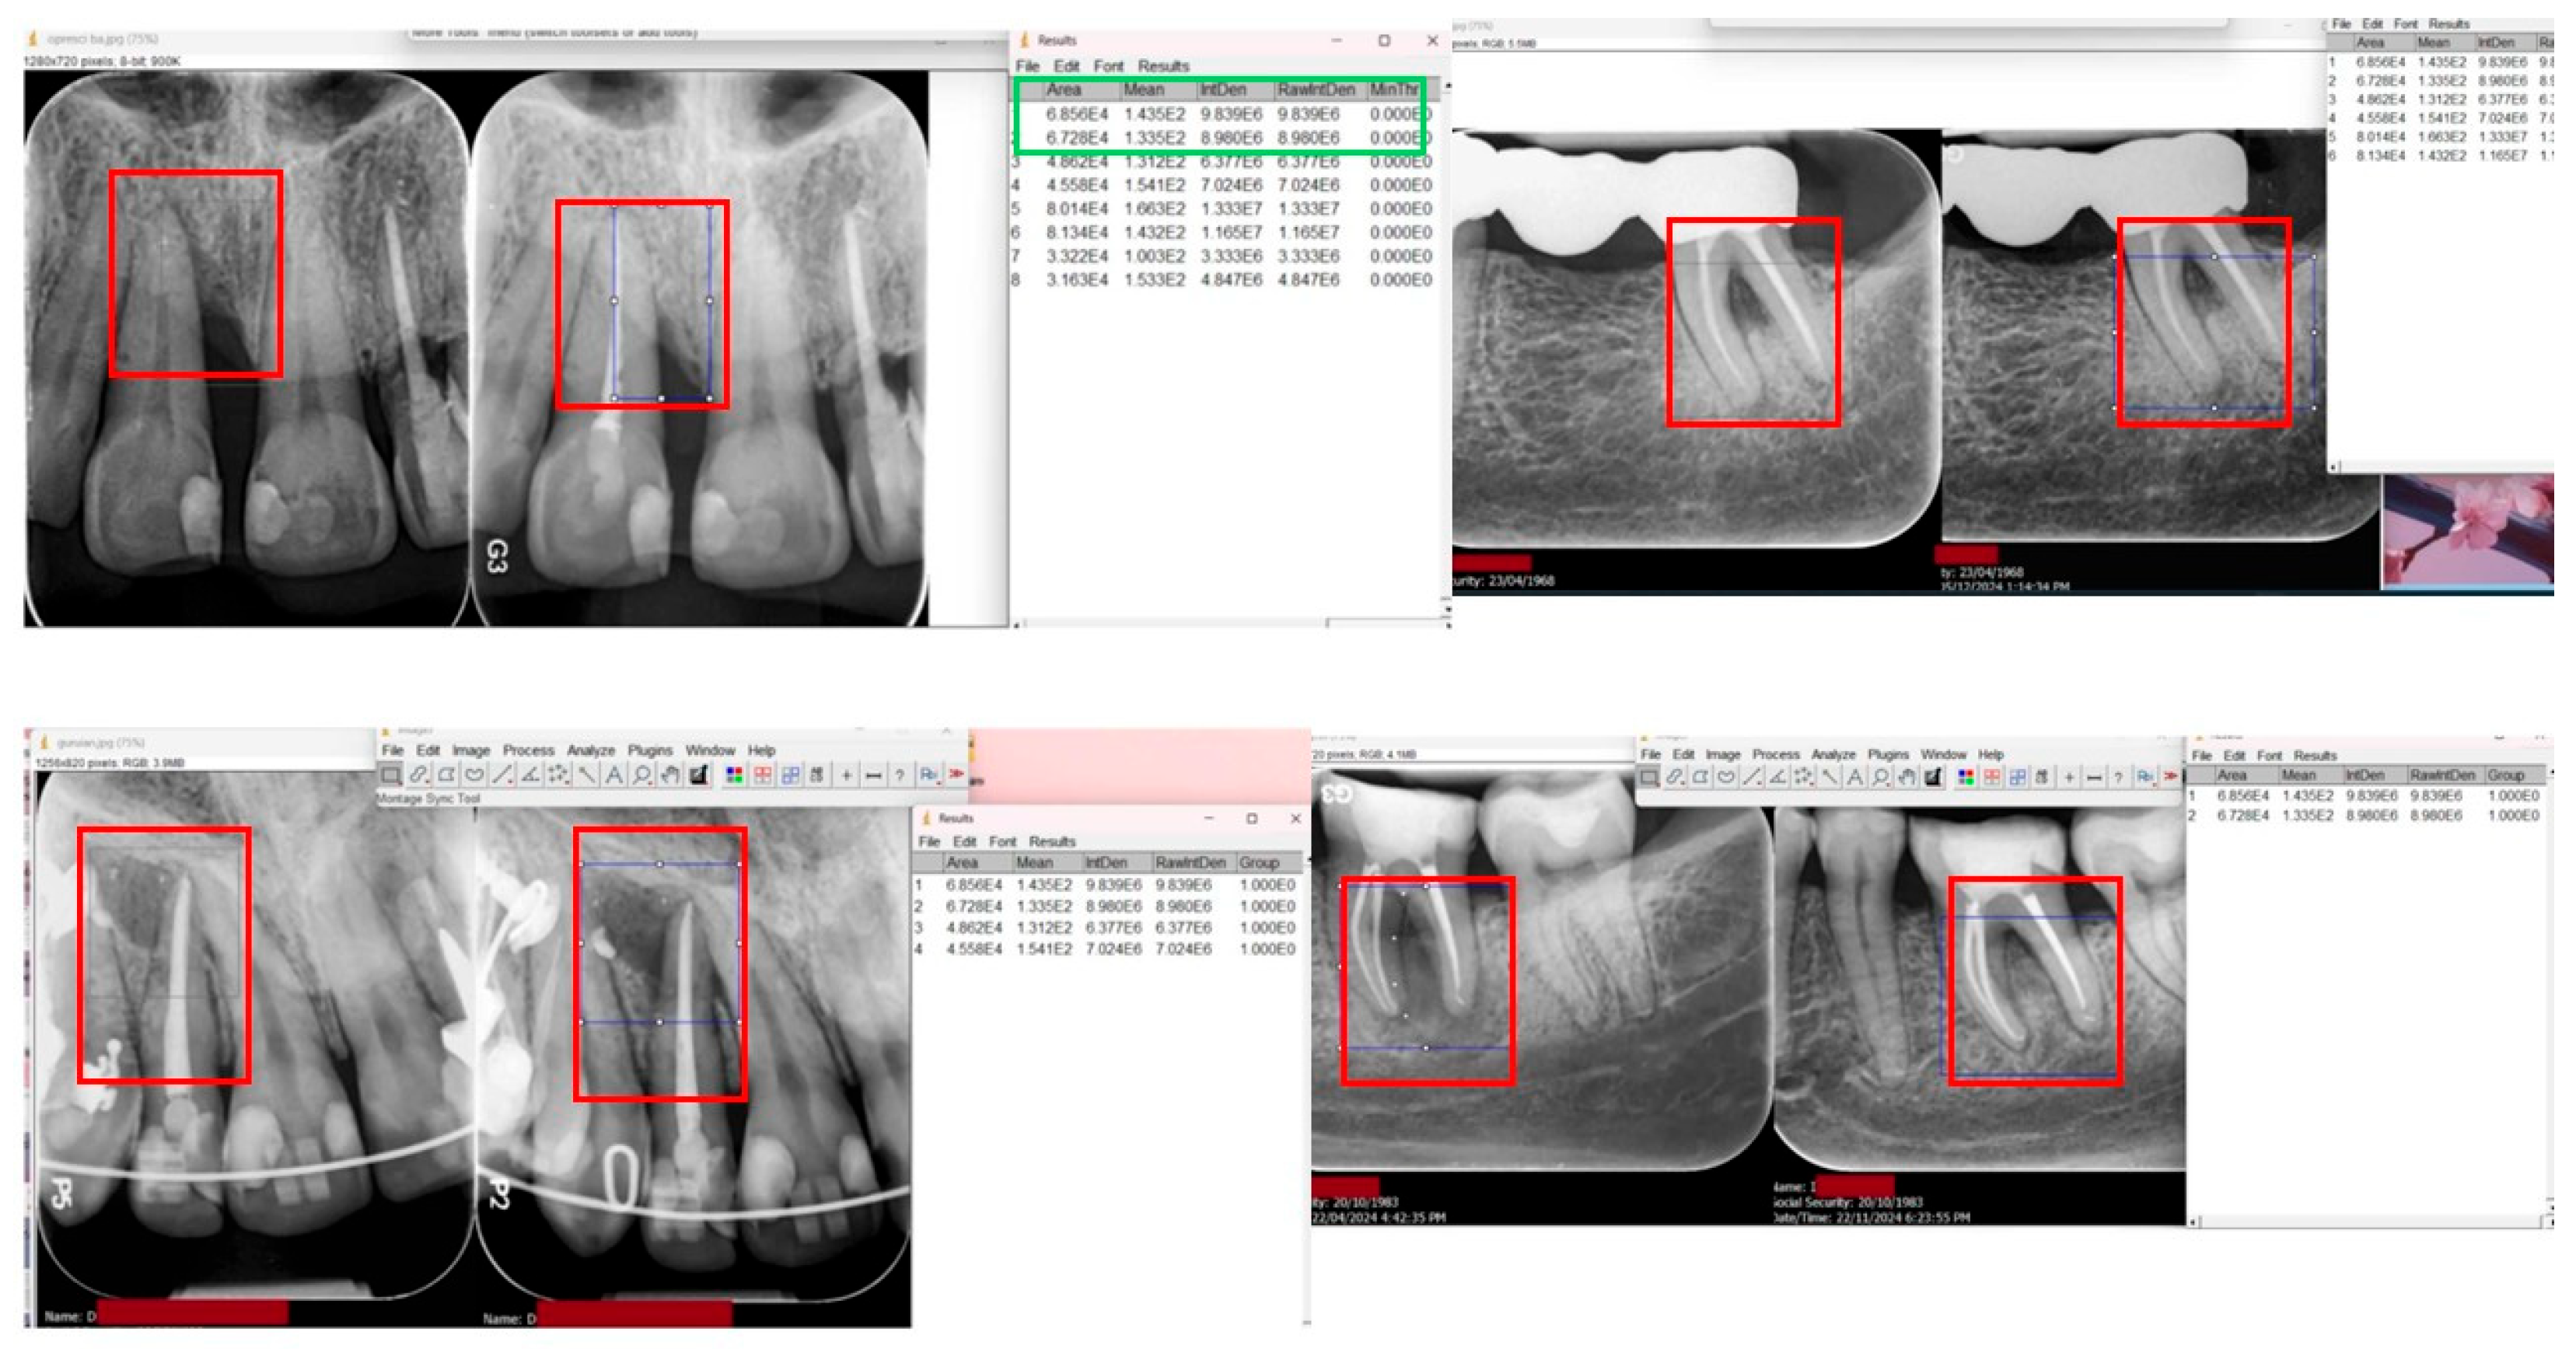

Radiographic Evaluation